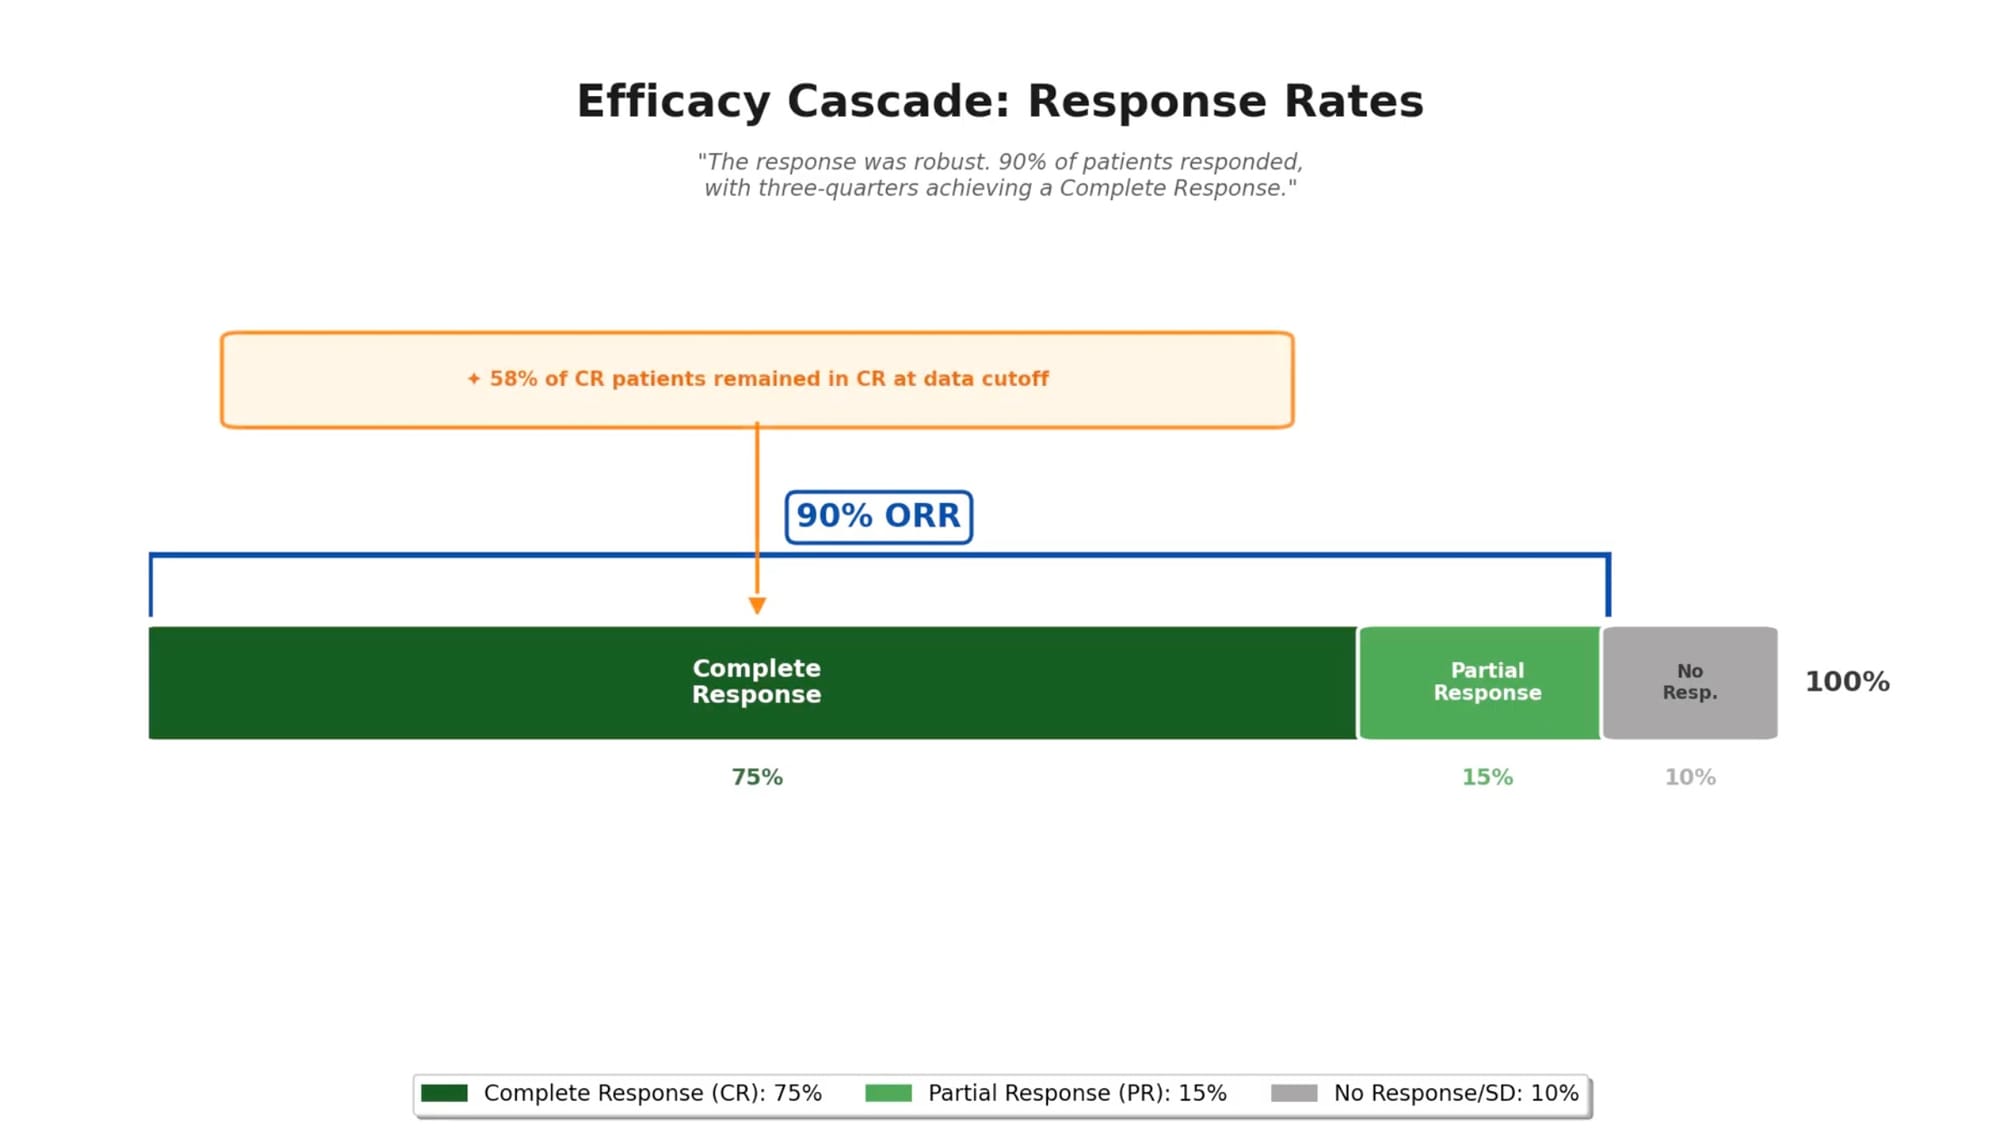

Efficacy: Durable Responses Over Five Years

After a median follow-up of 64.6 months—more than five years—the efficacy data demonstrate sustained benefit that extends well beyond what is typically seen with conventional therapies.

Response rates remained consistent with earlier analyses:

- Overall response rate: 90%

- Complete response rate: 75%

- Median time to best response: 1.0 month in follicular lymphoma

Durability proved to be the defining feature of these results:

- Median duration of response: 60.4 months

- Median progression-free survival: 62.2 months

- 50.4% of patients reached the 60-month progression-free survival landmark

- 58% of patients who achieved complete response remained in complete response at data cutoff

Perhaps most striking: at data cutoff, 55% of patients were alive without having required any subsequent anticancer therapy. For a population where the median prior therapies numbered three and the majority had refractory disease, this represents a meaningful departure from the expected trajectory.